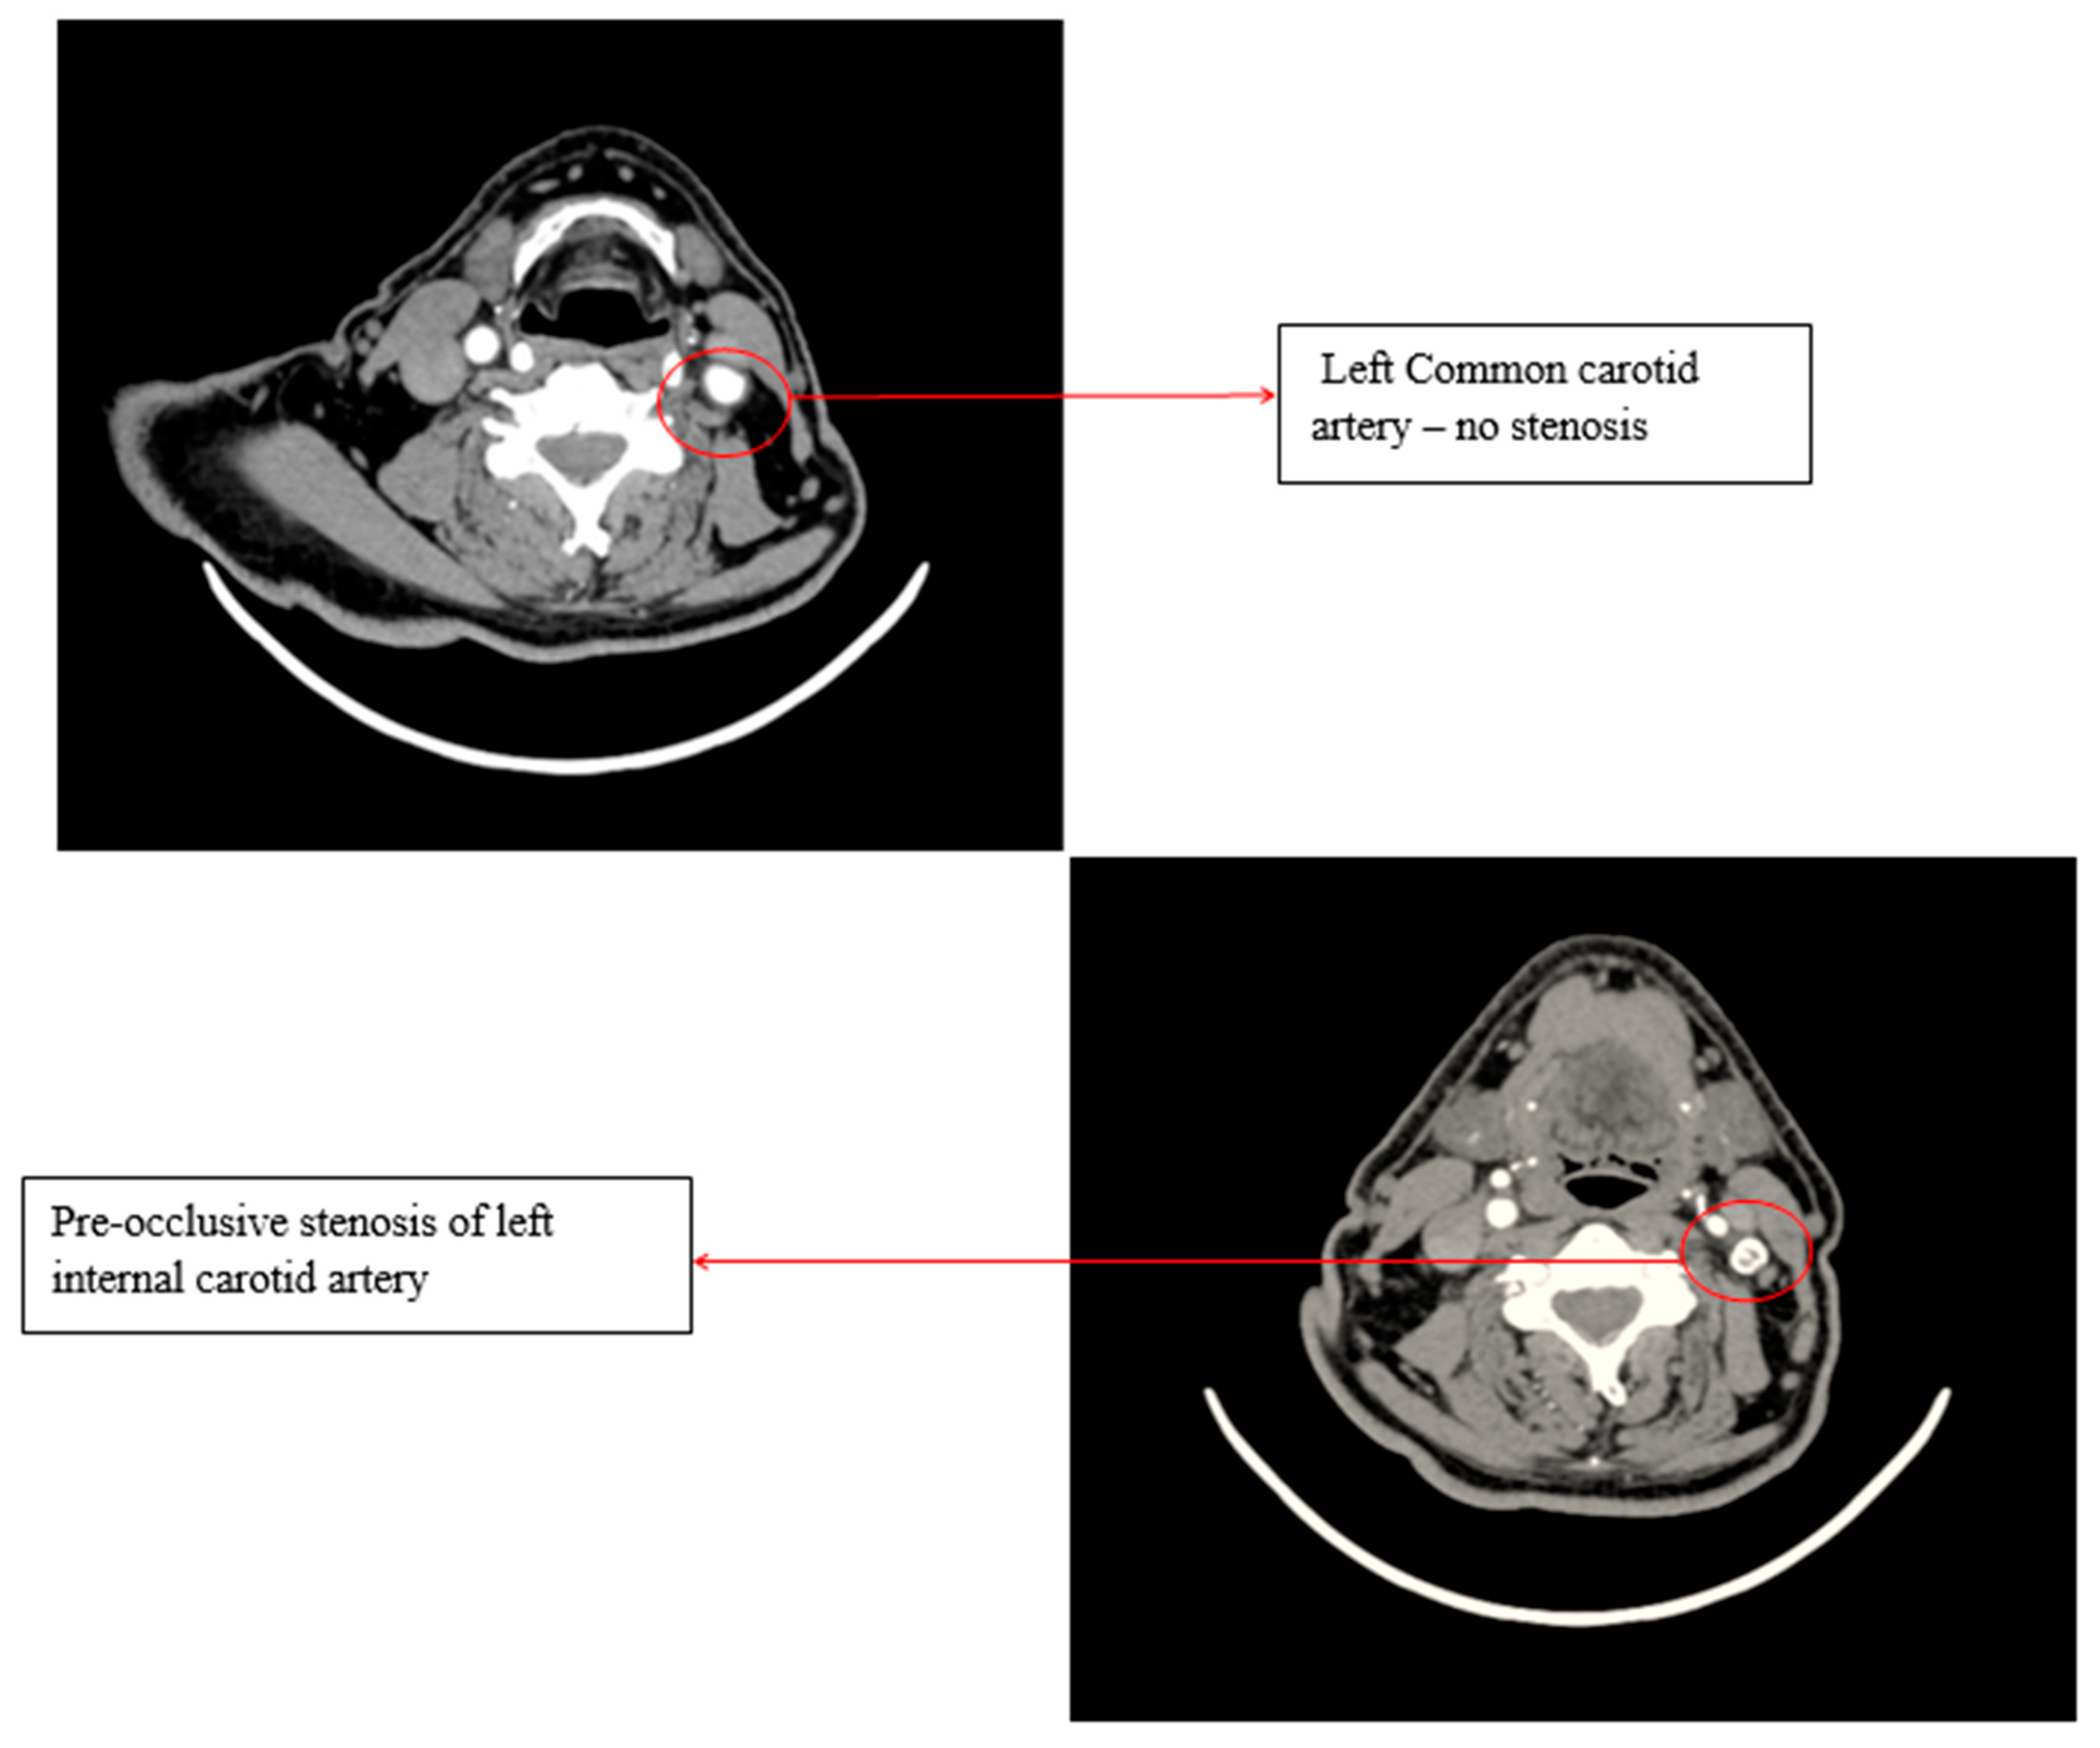

A Doppler ultrasound of the precerebral vessels, performed during the present admission, revealed a pre-occlusive stenosis of the left internal carotid artery, which was not present two years ago. This stenosis was confirmed by computed tomography angiography of the supra-aortic arteries (Figure 3).

Figure 3.

Computed tomography angiography (CTA) of the supra-aortic arteries.